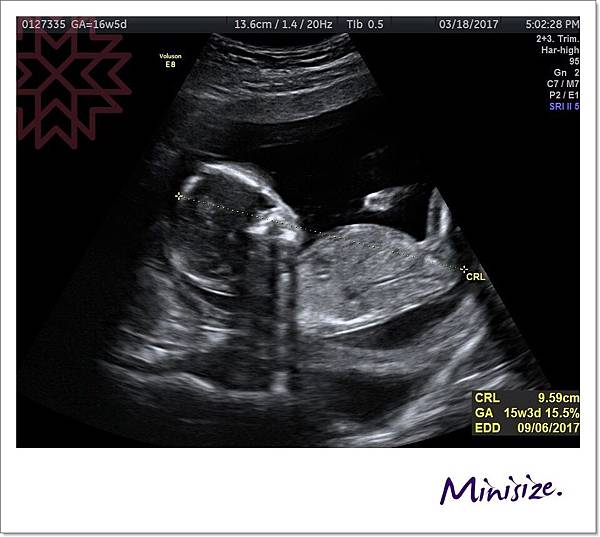

頭圍、頭臀圍、腿長、腦發育、心跳聲、子宮頸長度、羊水是否充足

才了解到原來我的大肚皮裡面藏一個頭臀圍長9.59公分的健康寶寶

聽到寶寶鏗鏘有力的心跳

真的好感動

小生命正在努力地長大中!